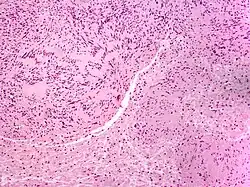

| Micrograph of a palisaded encapsulated neuroma | |

PEN is diagnosed by clinical recognition of the lesion and on subsequent histologic examination. Typically, the lesions are suspected to be schwannomas or neurofibromas clinically with PEN being an incidental finding on histology.[3]

PEN is typically diagnosed in patients between the ages of 40 and 60 years and occurs more frequently in females than males. The diagnosis of PEN may be difficult, even with confirmatory histology, due to its histological similarities with schwannomas and neurofibromas. It is imperative that the correct diagnosis is made the misdiagnosis of a neurofibroma may lead to unnecessary further investigation into associated systemic syndromes such as neurofibromatosis type 1 or multiple endocrine neoplasia syndrome.[3][4]